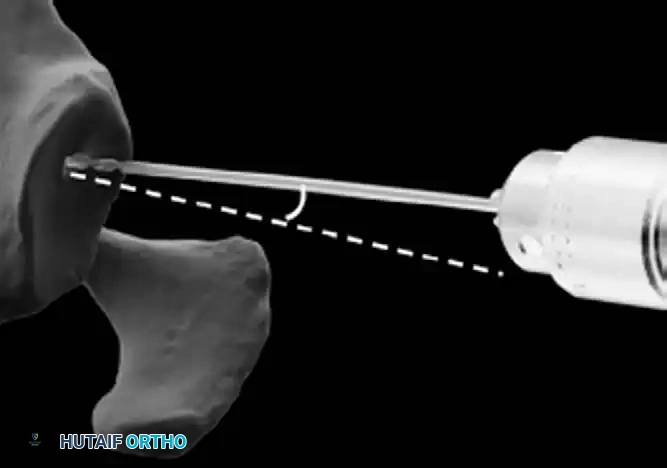

3. Humeral Head Resection

Dislocate the humeral head anteriorly through external rotation and extension. Remove peripheral osteophytes to identify the true anatomical neck. The humeral cut is made along the anatomical neck, typically at 30 degrees of retroversion and 45 degrees of inclination.